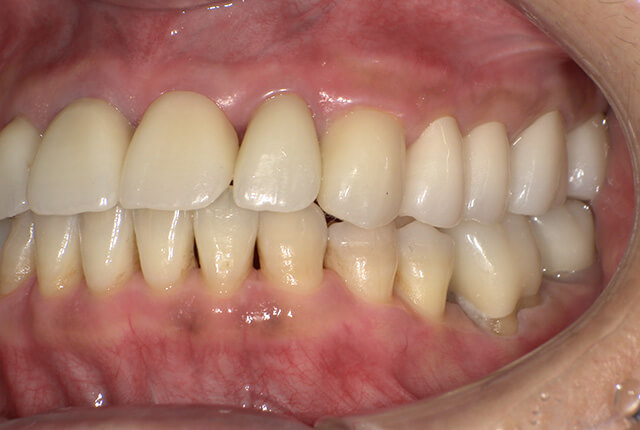

よく噛めず笑うと銀歯が目立つので気にされていました。

90分の治療で銀歯の状態からキレイな状態になります。噛み合わせの調整や審美面も使用しながら合わせます。

| 主訴 | ブリッジ脱離、しっかり噛めない |

| 主訴 | 噛めない、食事がしっかりできる様になりたい。 |

| 診査診断 | 歯周病、歯の崩壊、不良補綴。 全顎的咬合異常、前歯の噛み合わせ、奥歯の噛み合わせに問題あり。 |